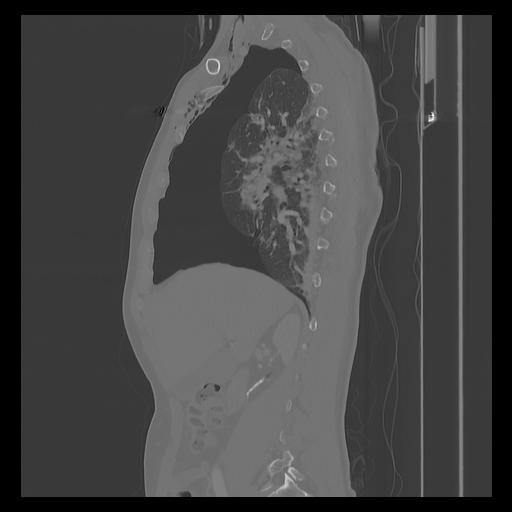

33 PULMON,CE,Sagittal,3.000,PULMON,Sagittal,